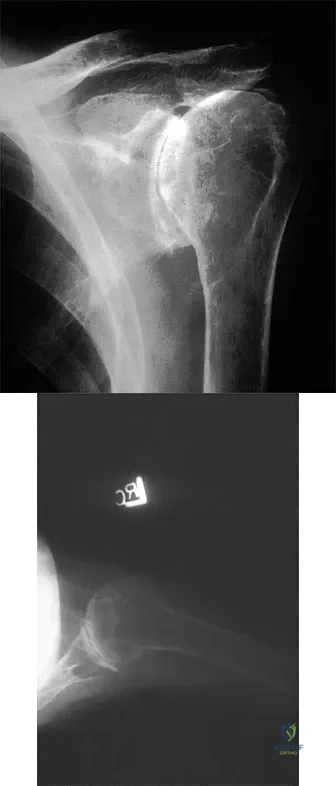

Question 70 High Yield

A 65-year-old woman sustained an axial load on the arm followed by an abduction injury after falling on ice. Treatment in the emergency department consisted of reduction of an anterior dislocation. She now has a positive drop arm sign and a positive lift-off test. An MRI scan is shown in Figure 9. Based on these findings, management should consist of

Detailed Explanation